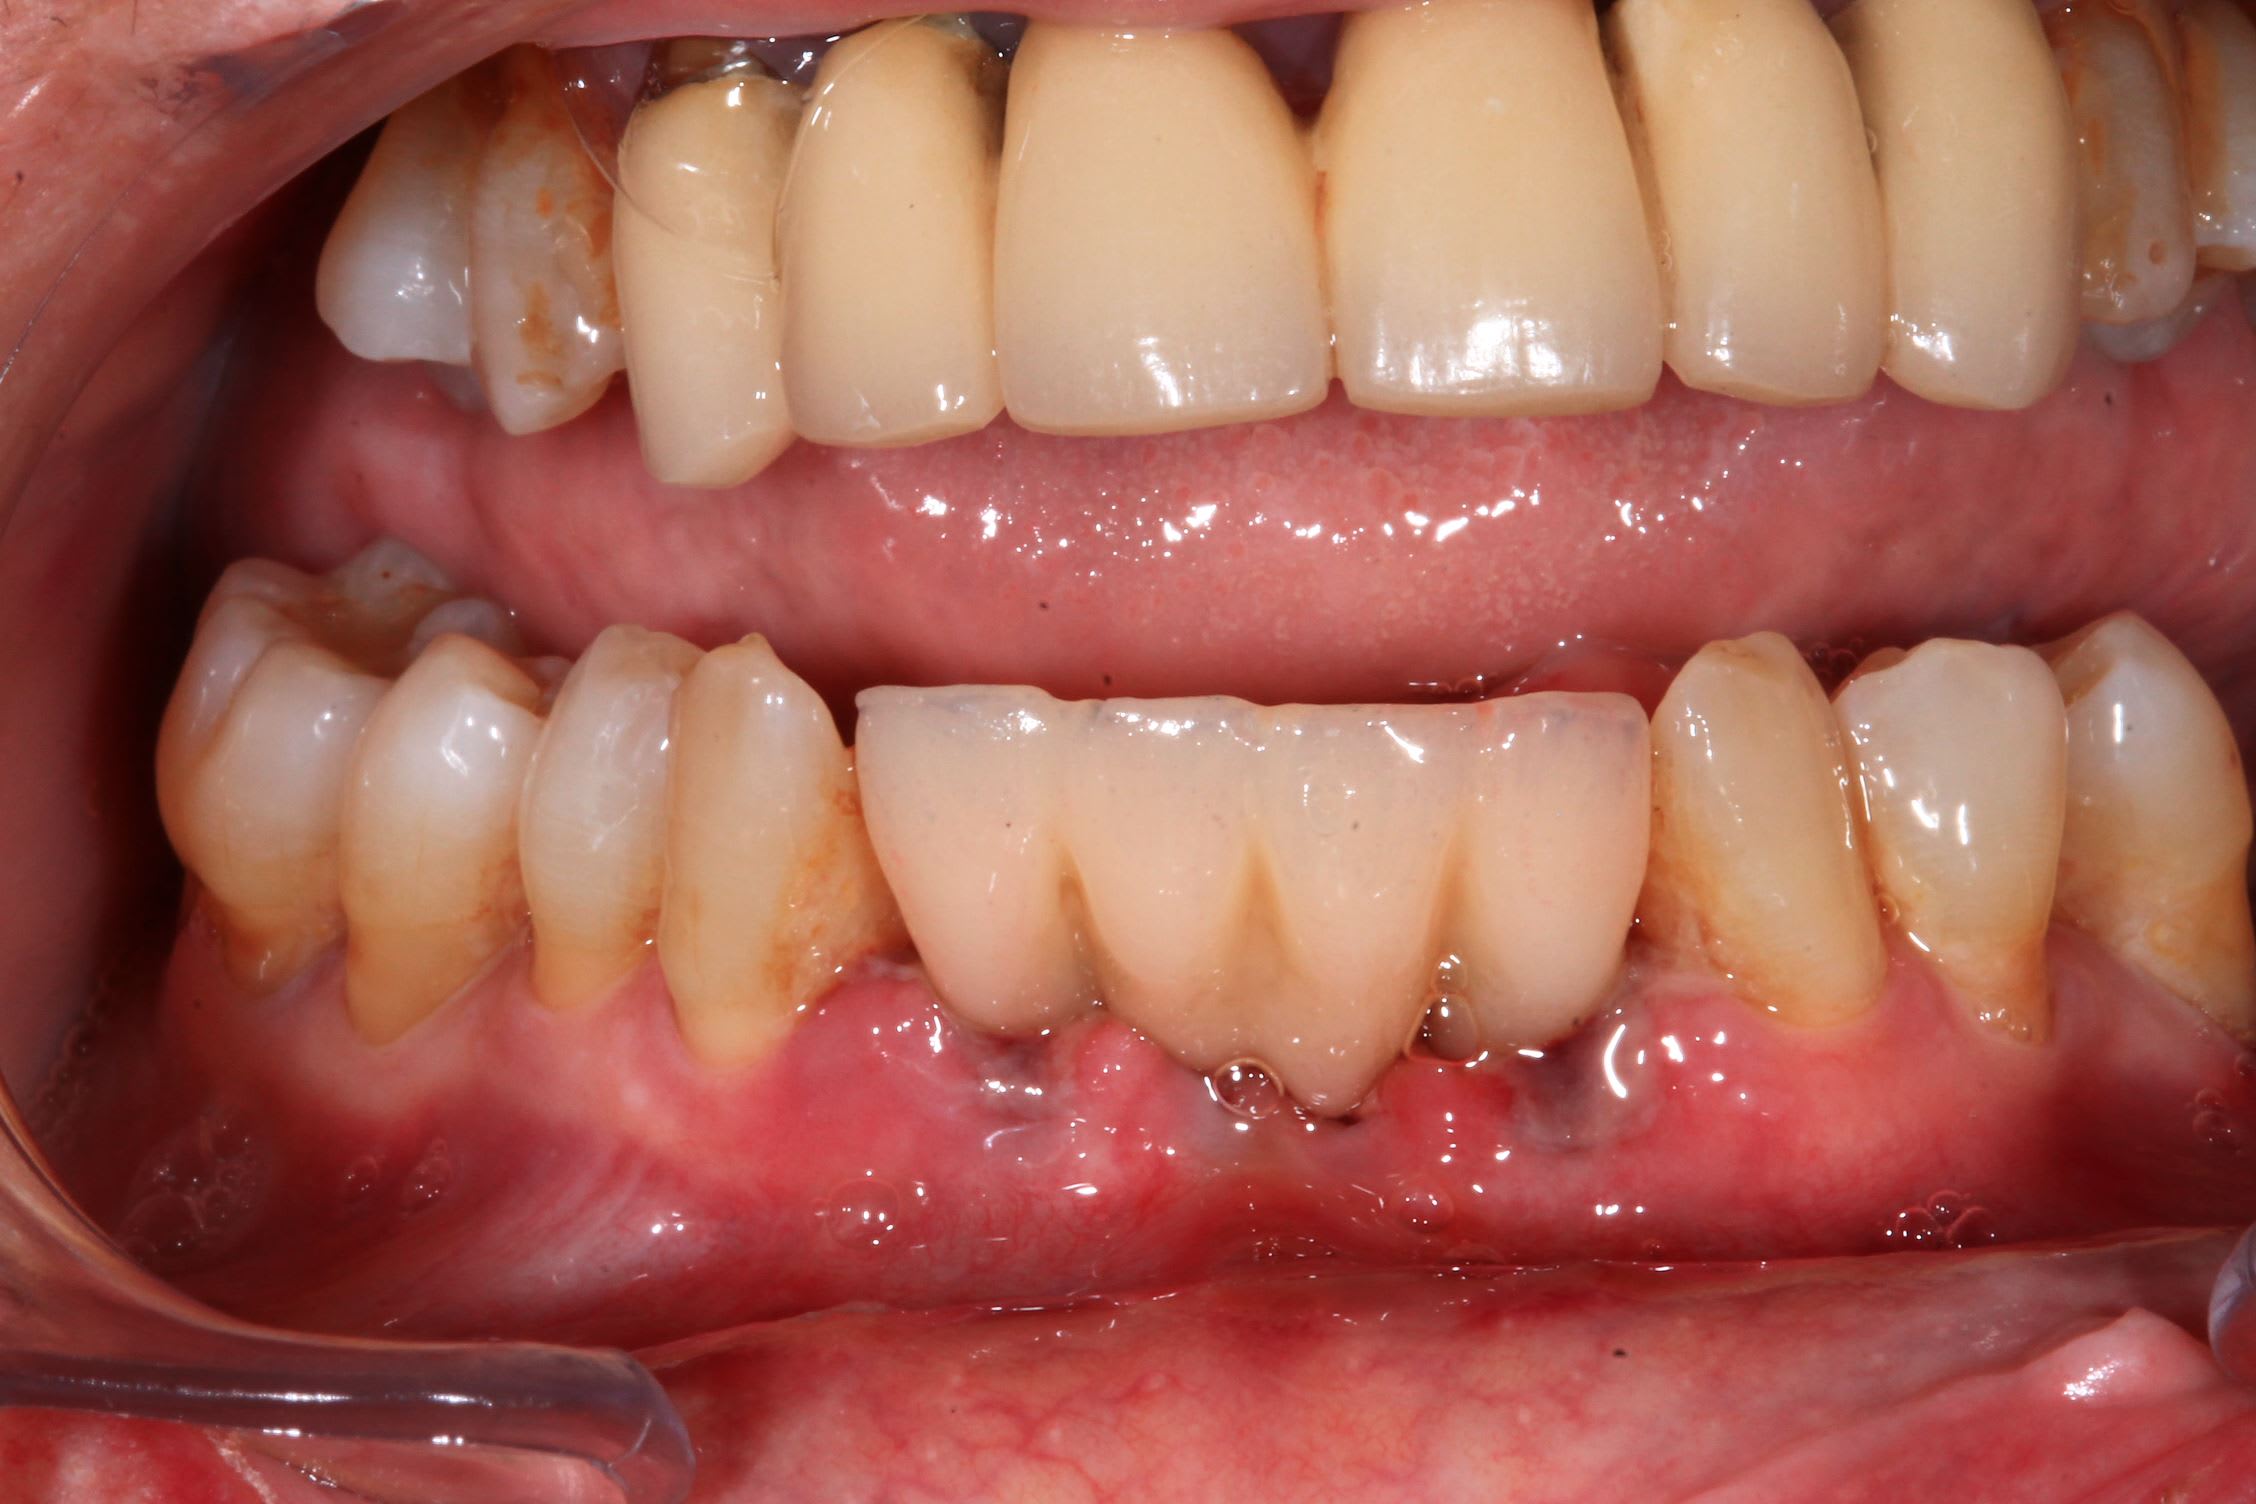

Autrement voici le prochain cas de pluton

Uzndgyh4j3jp73in0kayojbrs1b1 - Eugenol

Sekb7wvvo0auhvpkhvkytxt67oyf - Eugenol

pluton

06/07/2022 à 18h08

> Autrement voici le prochain cas de pluton

Et c'est toujours possible de venir découvrir avec moi....intervention le 21/07 prochain à partir de 9h00